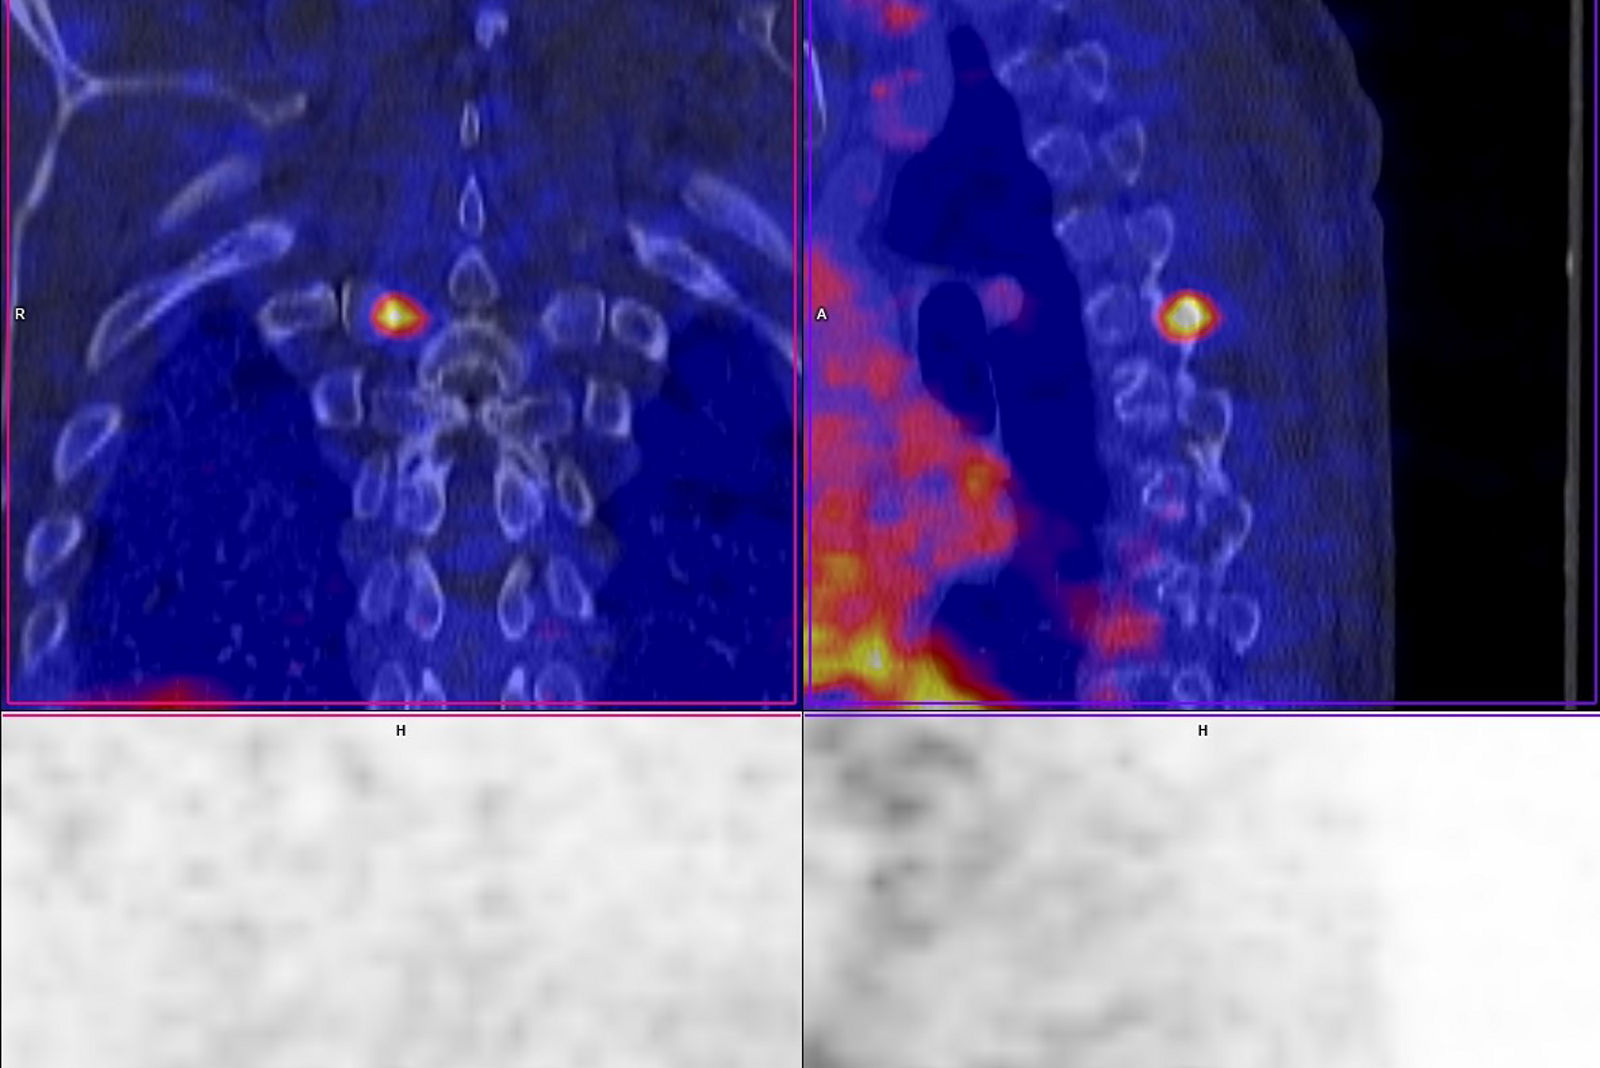

Die PET stellt durch den Einsatz schwach radioaktiver Substanzen unterschiedliche Stoffwechselvorgänge dar, die durch die Kombination mit der CT dann genau anatomisch zugeordnet werden können. Dadurch wird insbesondere in der Onkologie eine präzise und rasche Lokalisation von Tumorgewebe (Primärtumoren oder auch Metastasen) möglich und eine Therapie kann gezielter geplant werden. Manche Therapie wird durch die PET-CT in eine andere Richtung gelenkt, unnötige Therapien werden vermieden.

Der Schwerpunkt der PET-CT-Diagnostik liegt in der Onkologie. Aber auch bei neurologischen oder kardiologischen Fragenstellungen ist diese Form der Diagnostik von großer Bedeutung. Insbesondere bei der Diagnostik von Bronchialkarzinomen ist das Gerät sehr wertvoll. Seit 2010 ist die PET-CT-Untersuchung vor einem operativen Eingriff aufgrund von Lungenkrebs in den Behandlungsleitlinien festgeschrieben. Das Gerät stärkt somit die Leistungskraft des Bergischen Lungenzentrums. Um die fachübergreifende Nutzung des Gerätes zu vereinfachen und Behandlungen für den Patienten zu optimieren, sind die erzeugten Aufnahmen im gesamten System der Klinik nutzbar.